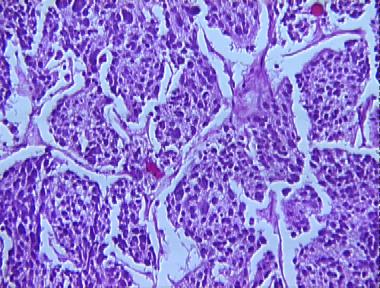

neuroblastoma

Histologic Features